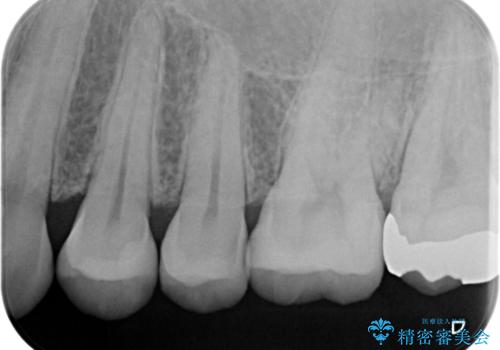

- 銀歯のやり替えと虫歯の治療をご希望で来院された患者様です。

一番奥の歯は外から見えにくい部分であるためゴールドインレーで修復します。

その他はセラミックインレーで修復します。

- 左上46:セラミックインレー/77,000円×2 左上7:ゴールドインレー/77,000円×1費用は治療当時の料金となります

噛みしめの強い方や、外から見えないような部分では、割れる心配のないゴールドインレーをおすすめします。